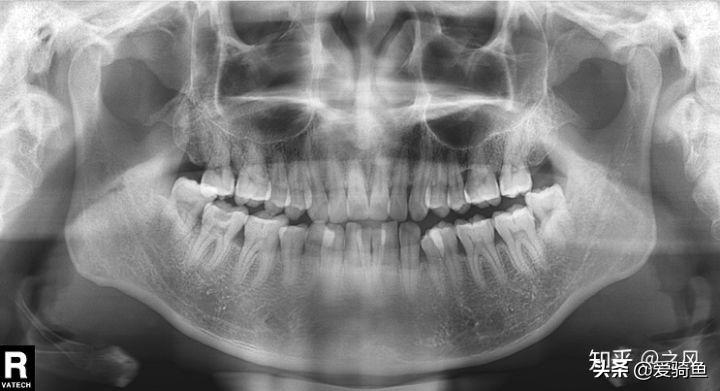

排隊(duì)等待叫號,進(jìn)去后張嘴檢查下,讓去拍片子,應(yīng)該就是我之前去的其他牙診所機(jī)構(gòu)的口掃,這里沒有給我電子照片,下面是以前拍的。

口掃

智齒